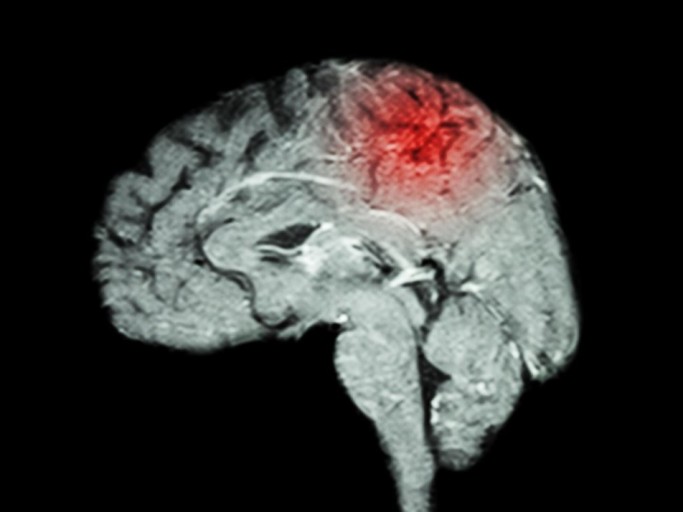

뇌출혈은 뇌혈관이 파열되어 뇌에 출혈이 발생하는 질환으로, 매우 급격하게 발생할 수 있으며 생명에 위협을 줄 수 있습니다. 하지만 뇌출혈이 발생하기 전에 나타날 수 있는 전조증상을 잘 인식하고 빠르게 대처하는 것이 중요합니다. 아래에 뇌출혈의 11가지 전조증상을 아주 자세히 설명하겠습니다.